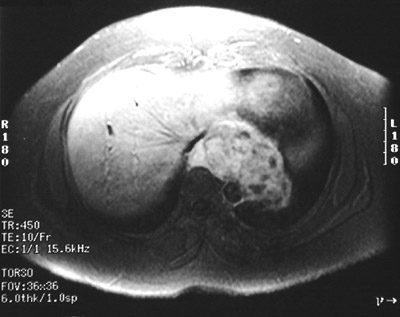

| There is a gastrointestinal stromal tumor (GIST) involving the lower esophagus and extending to the upper gastric fundus in this MRI scan. This is a gastrointestinal stromal tumor (GIST). These tumors were once called leiomyomas, but are now thought to arise from a myenteric plexus cell. |